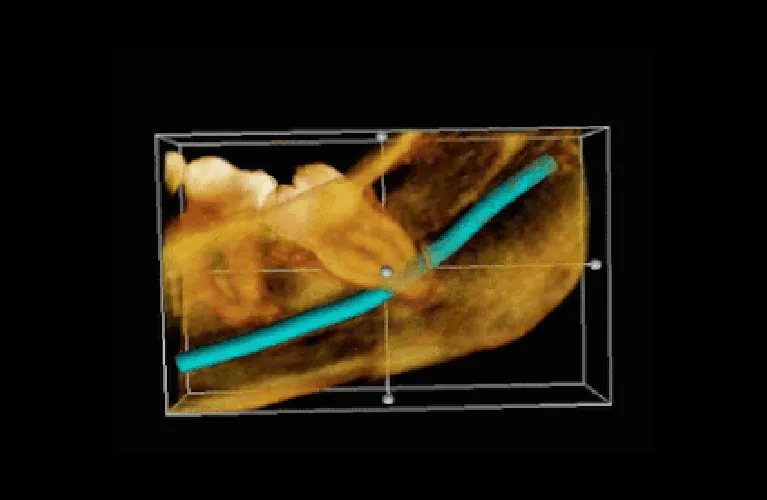

Pre-Operative Xray Required

OPG

CBCT